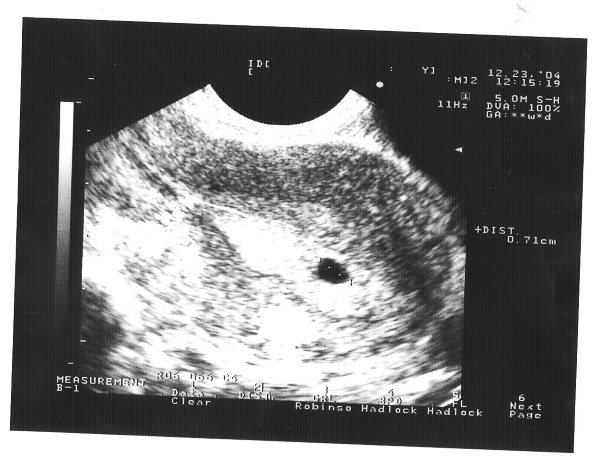

Что видно на УЗИ?

Беременность 5 акушерских недель – это ещё очень ранний срок, но сканирование можно провести, и с его помощью выявить некоторые как положительные, так и отрицательные признаки гестации.

Что можно увидеть на экране:

- Виден гестационный мешок в виде чёрной области, его размер не более 12 мм.

- В верхнем левом углу мешка просматривается желточное тело, которое является питательным источником для плода.

- Эмбрион меньше, чем рисовое зерно.

- Возможно два желточных мешка, это говорит о развитии близнецов (двойняшек).

Опытный диагност может обнаружить желточный мешок. В этот период он представлен в виде колечка 3–4 мм размером, на котором и сидит эмбрион-головастик, размером от 8 до 10 мм. Наличие мешка подтверждает диагноз внутриутробной и исключает внематочную беременность. Редко возникают случаи одновременного развития внутриутробного и внематочного плода.

Проверяется состояние жёлтого тела в яичниках, которое обеспечивает гармоничное развитие беременности, обеспечивает зародыш питанием и дыханием, но в большей степени от него зависит система кроветворения эмбриона. При трансвагинальном УЗИ иногда наблюдаются сердечные сокращения у эмбриона размером от 2 до 3 мм. В конце 5 недели частота сердечных сокращений достигает 60-90 ударов в минуту.

Но реальная частота сокращений в этот период не так важна, как её наличие или отсутствие. Показания для УЗИ разделяются на скрининговые и селективные. Первые проводятся у всех будущих мам и назначают их для выявления пороков развития плода. Для этого измеряется его размер, соответствие его сроку беременности, производится осмотр плаценты и матки.